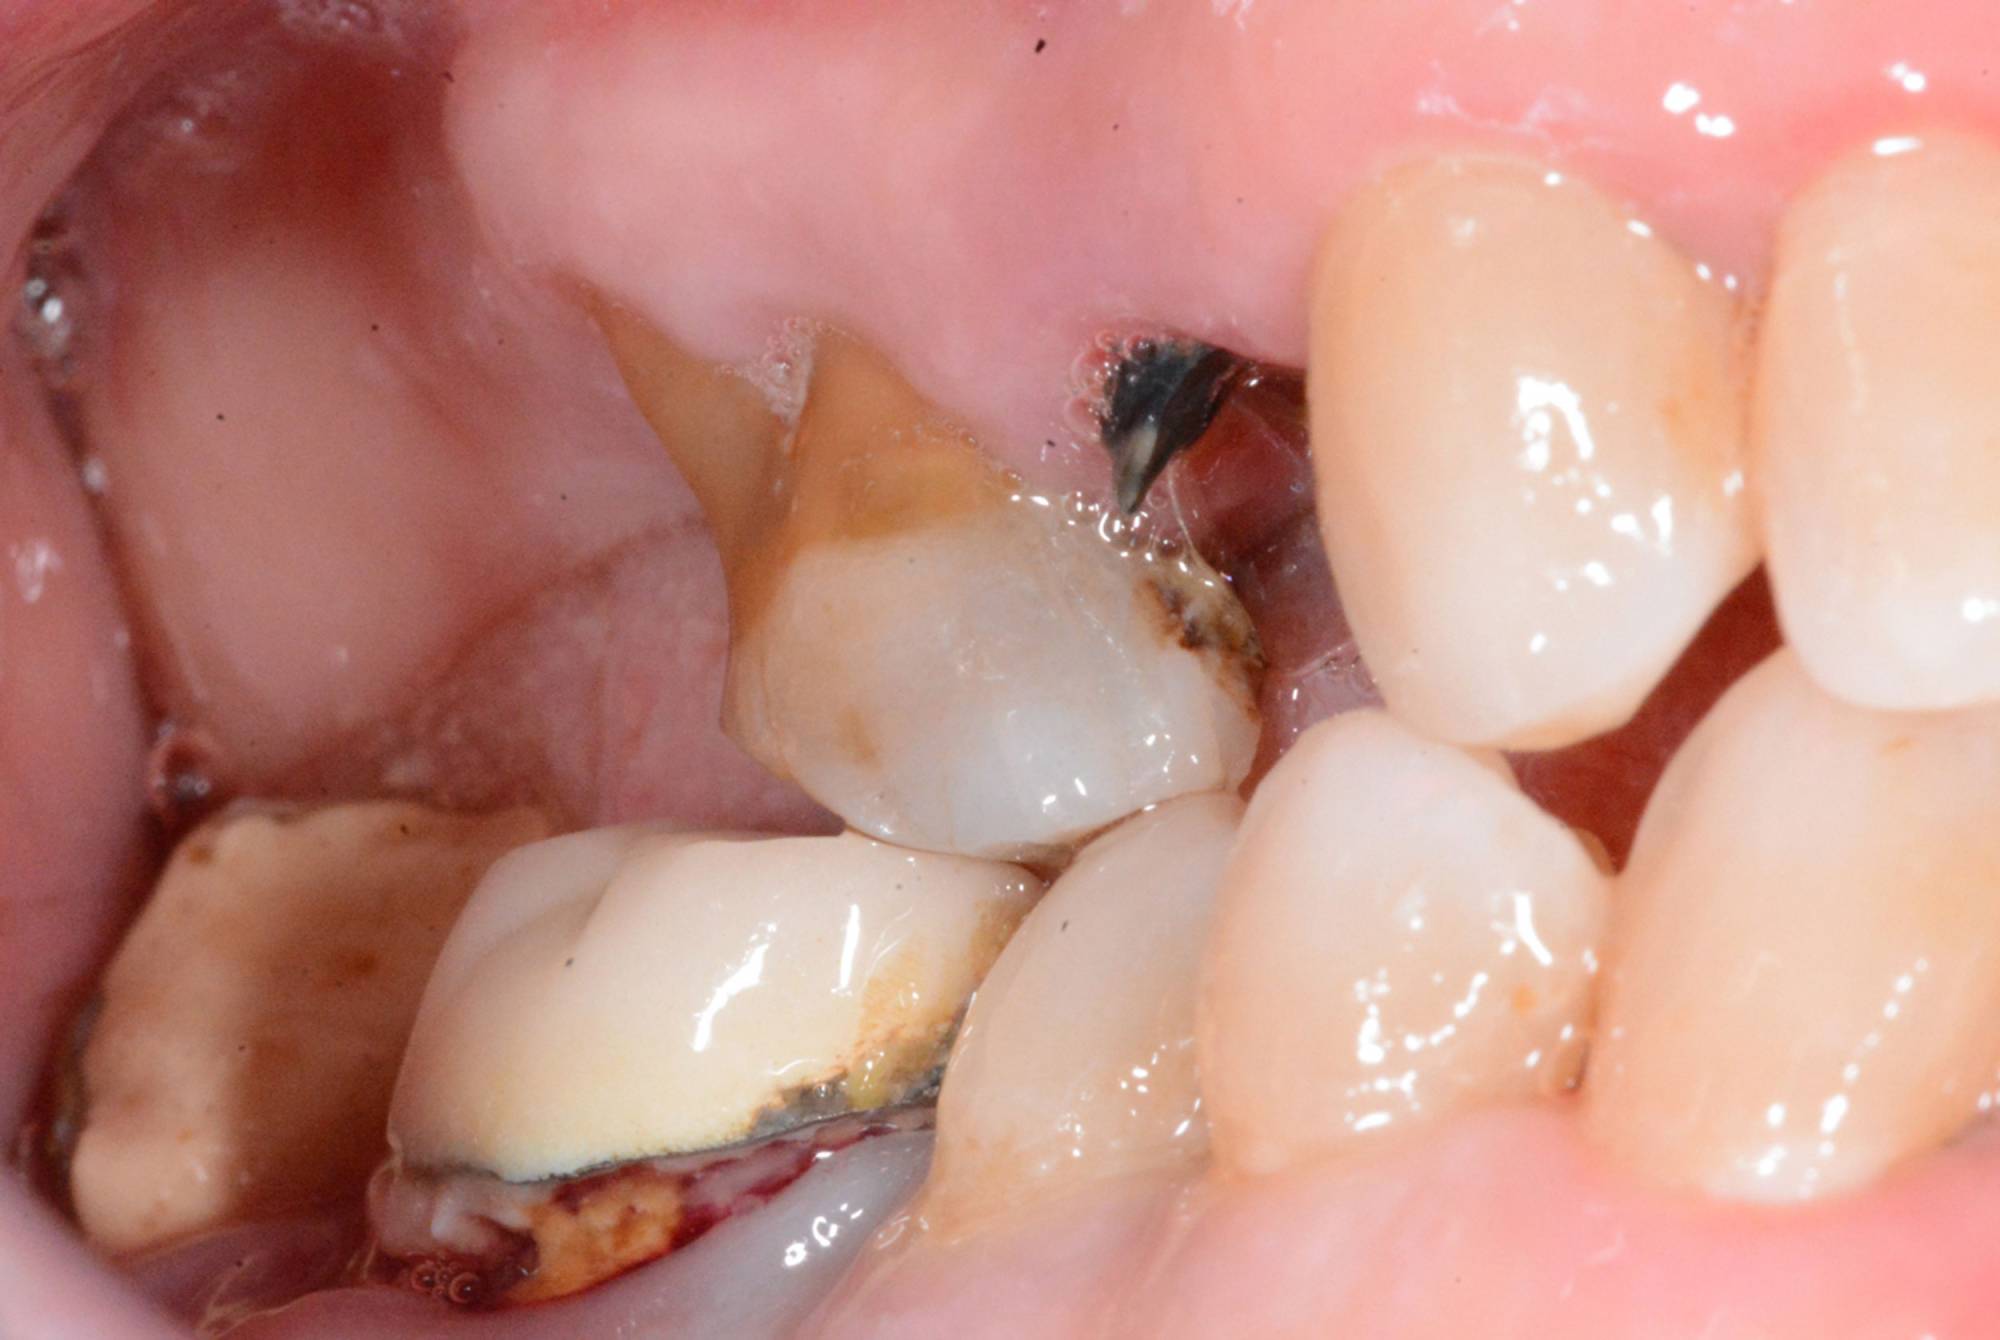

Quasi tutti possono ricorrere agli impianti, poiché sono una soluzione che presenta solo poche controindicazioni di carattere generale. Anche nei casi in cui non vi sia una sufficiente quantità d’osso per inserire l’impianto, è possibile ricorrere a tecniche di rigenerazione ossea guidata utilizzando biomateriali specifici e porzioni d'osso prelevate dal paziente stesso, per ricostruire la parte ossea mancante.

Generalmente devono trascorrere alcuni mesi tra l’intervento chirurgico di inserimento di un impianto e la realizzazione della protesi da fissare ad esso.

In questo lasso di tempo, nel quale l'impianto è sommerso sotto la gengiva e si avvia il processo di guarigione ossea, si realizza l'osteointegrazione, ovvero un intimo contatto fra l’osso e la superficie biocompatibile in titanio dell’impianto.